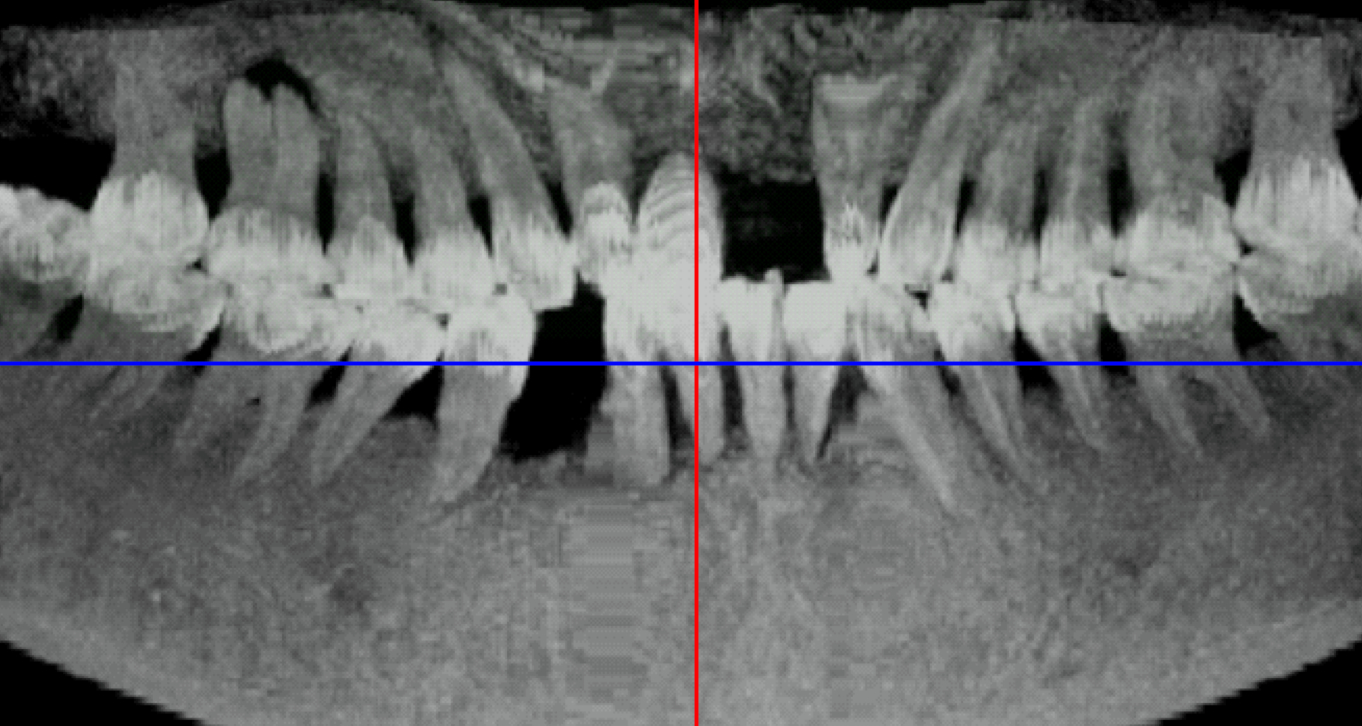

CPR

典型的曲面重建啊

找到一个这个图,大概描绘了实现过程。只不过从曲线到直线我现在是逐点幅值的,要是有个映射函数就好了,应该有,我还没找。

《口腔全景锥形束 CT 图像重建算法 》里的内容,希望有帮助